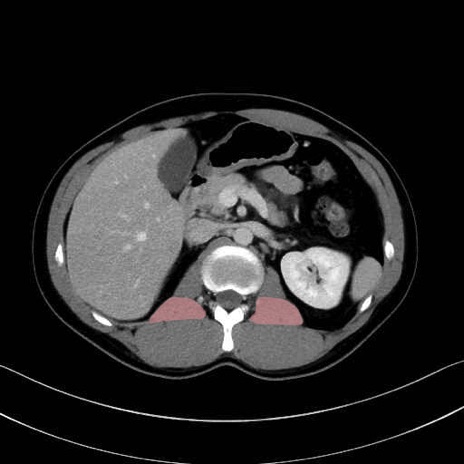

腰方形筋(quadratus lumborum muscle)のCT画像の解剖

腰方形筋 (Quadratus lumborum)